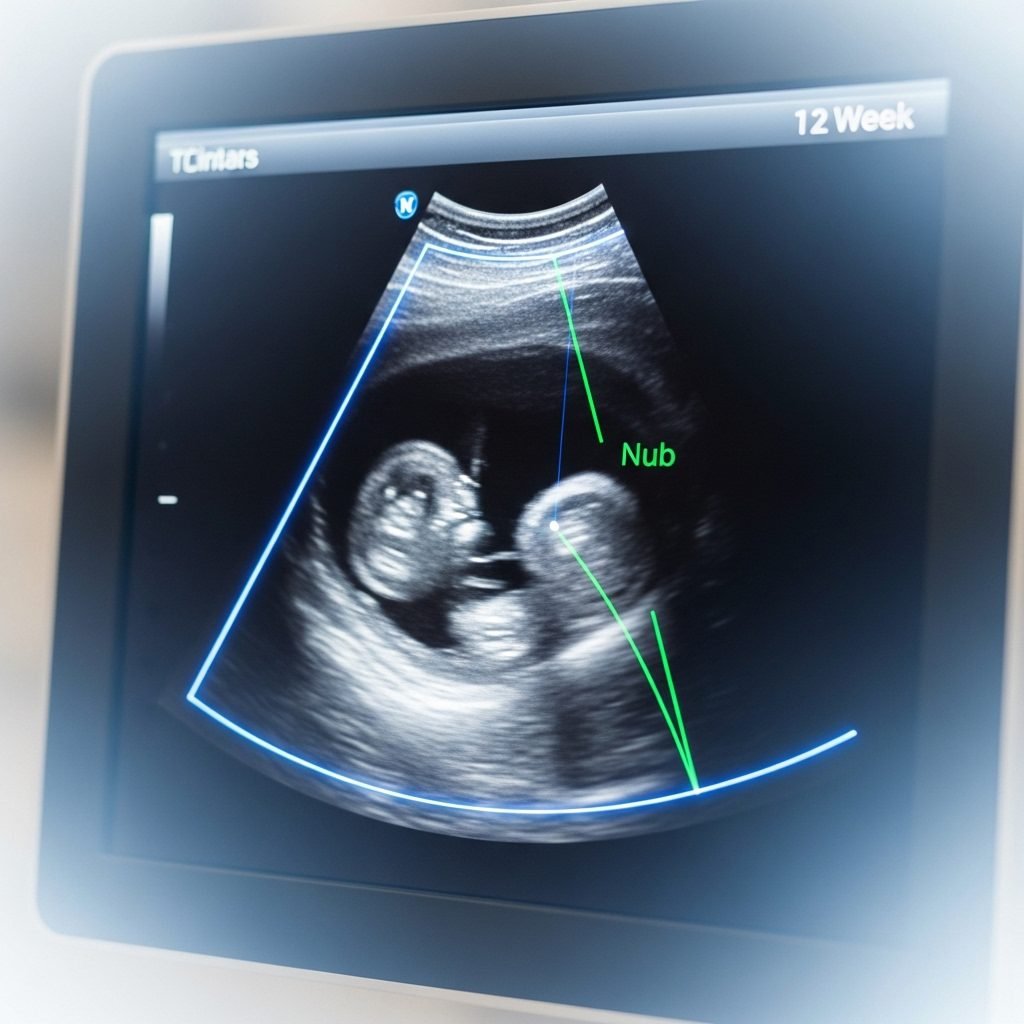

At its heart, the Nub Theory is all about looking at the ‘angle of the dangle.’ It sounds playful, but it’s based on early fetal development. Between 11 and 14 weeks of gestation, both male and female fetuses have a small protuberance between their legs called the genital tubercle. To the untrained eye, they look virtually identical. However, the secret lies in the direction this ‘nub’ is pointing in relation to the baby’s spine.

Think of it as the very first sign of differentiation. Before the genitals are fully formed and clearly identifiable as male or female, the angle of this tubercle offers a significant clue. Here’s the basic principle:

- For a Boy: The genital tubercle (nub) will be pointing upwards, at an angle of 30 degrees or more relative to the lower part of the spine.

- For a Girl: The genital tubercle (nub) will be pointing straight out, nearly parallel to the spine, at an angle of less than 30 degrees.

It’s a subtle difference, but one that becomes more pronounced as the weeks go by. The theory relies on observing this specific anatomical relationship in a clear profile image of the fetus. It’s a fascinating glimpse into the intricate process of development happening inside the womb, turning a standard medical check-up into a moment of playful detection for hopeful parents.

- Get the Right Picture: The key to the Nub Theory is a clear, side-profile (sagittal) view of your baby. The baby needs to be lying relatively flat. An image of the baby curled up in a ball or facing forward won’t work. Ask your sonographer if they can capture a good profile shot for you.

- Identify the Spine: First, locate your baby’s spine. It will look like a bright, white line running along their back. You need this as your baseline for measuring the angle.

- Find the Nub: Look towards the bottom end of the baby, between the legs. You should see a small, bright white nub sticking out. This is the genital tubercle.

- Assess the Angle: Now, imagine a line running through the lower part of the spine. Then, imagine another line running through the nub. What is the angle between them? Is the nub pointing up (like a little ski jump) or is it running flat and parallel to the spine?